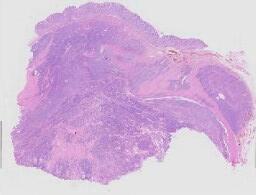

临床资料: 女,23岁,腹痛入院,彩超提示右侧附件区不均质回声。

大体所见: (右侧卵巢囊肿):灰红碎组织一堆,大小共约11×10×2.5cm,内有囊壁样组织及血凝块,囊壁较光滑,部分实性组织切面灰白、质中。